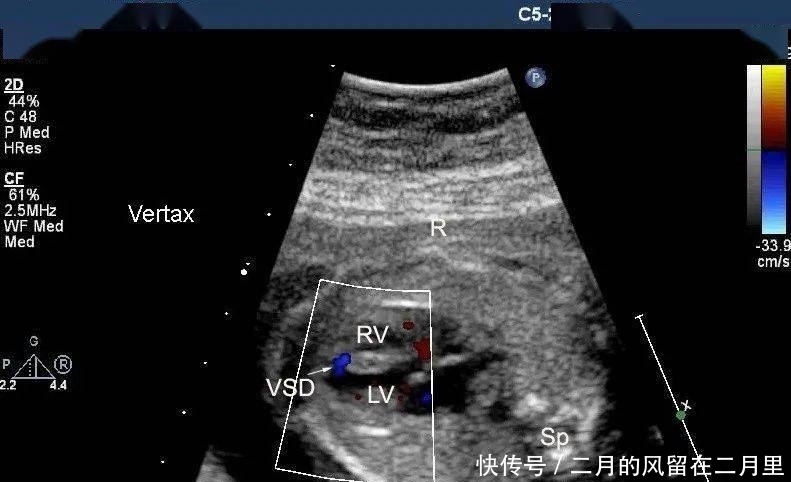

以下是我们掌中宝里几张图,很典型,很清晰。

VSD的超声声像图特征:

(1)室间隔连续性中断,缺损部位断端“回声增强”;

(2)缺损处出现双向分流,CDFI检测可见不同时相红蓝双向的血流